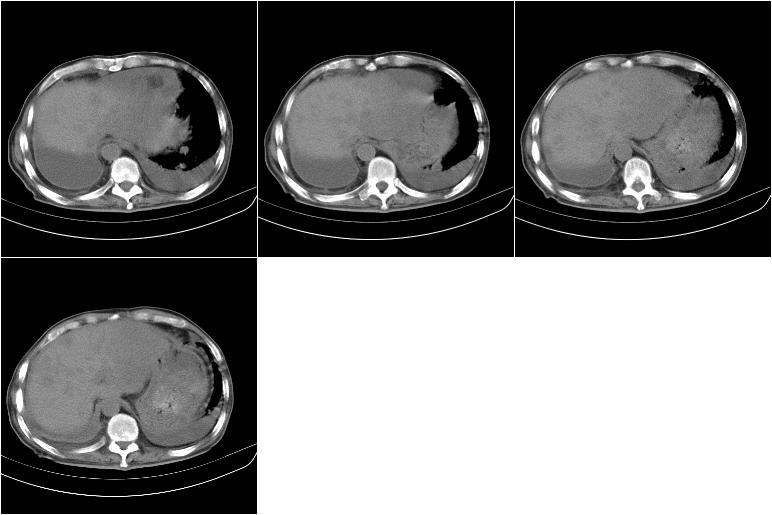

以下是引用边生丽在2009-8-17 11:43:00的发言:[br][br] [br] 右肺中心型癌伴右肺下叶不张、双肺转移并癌性淋巴管炎、心包和双侧胸腔积淮(转移?)、脑转移、肝转移、多骨(颅骨、椎骨)转移。 [br] [br]

以下是引用随光逐影在2009-8-17 14:09:00的发言:[br]支持 右肺中央型癌伴右肺下叶肺不张,纵隔淋巴结转移,双肺转移并癌性淋巴管炎,心包和双侧胸腔积液,脑转移、肝转移、多发性骨(颅骨、脊椎)转移。